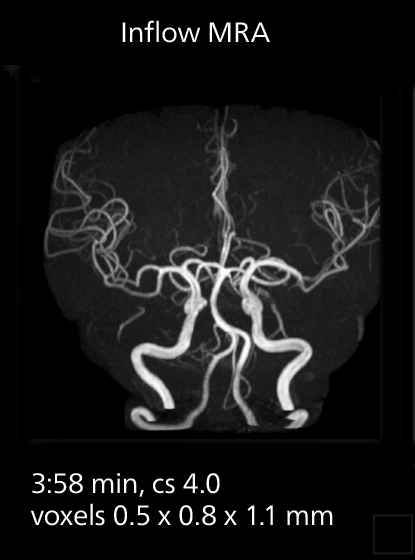

Brain MRI

These images of an old cerebral infarction demonstrate the speed and image quality after upgrading to Elition X.